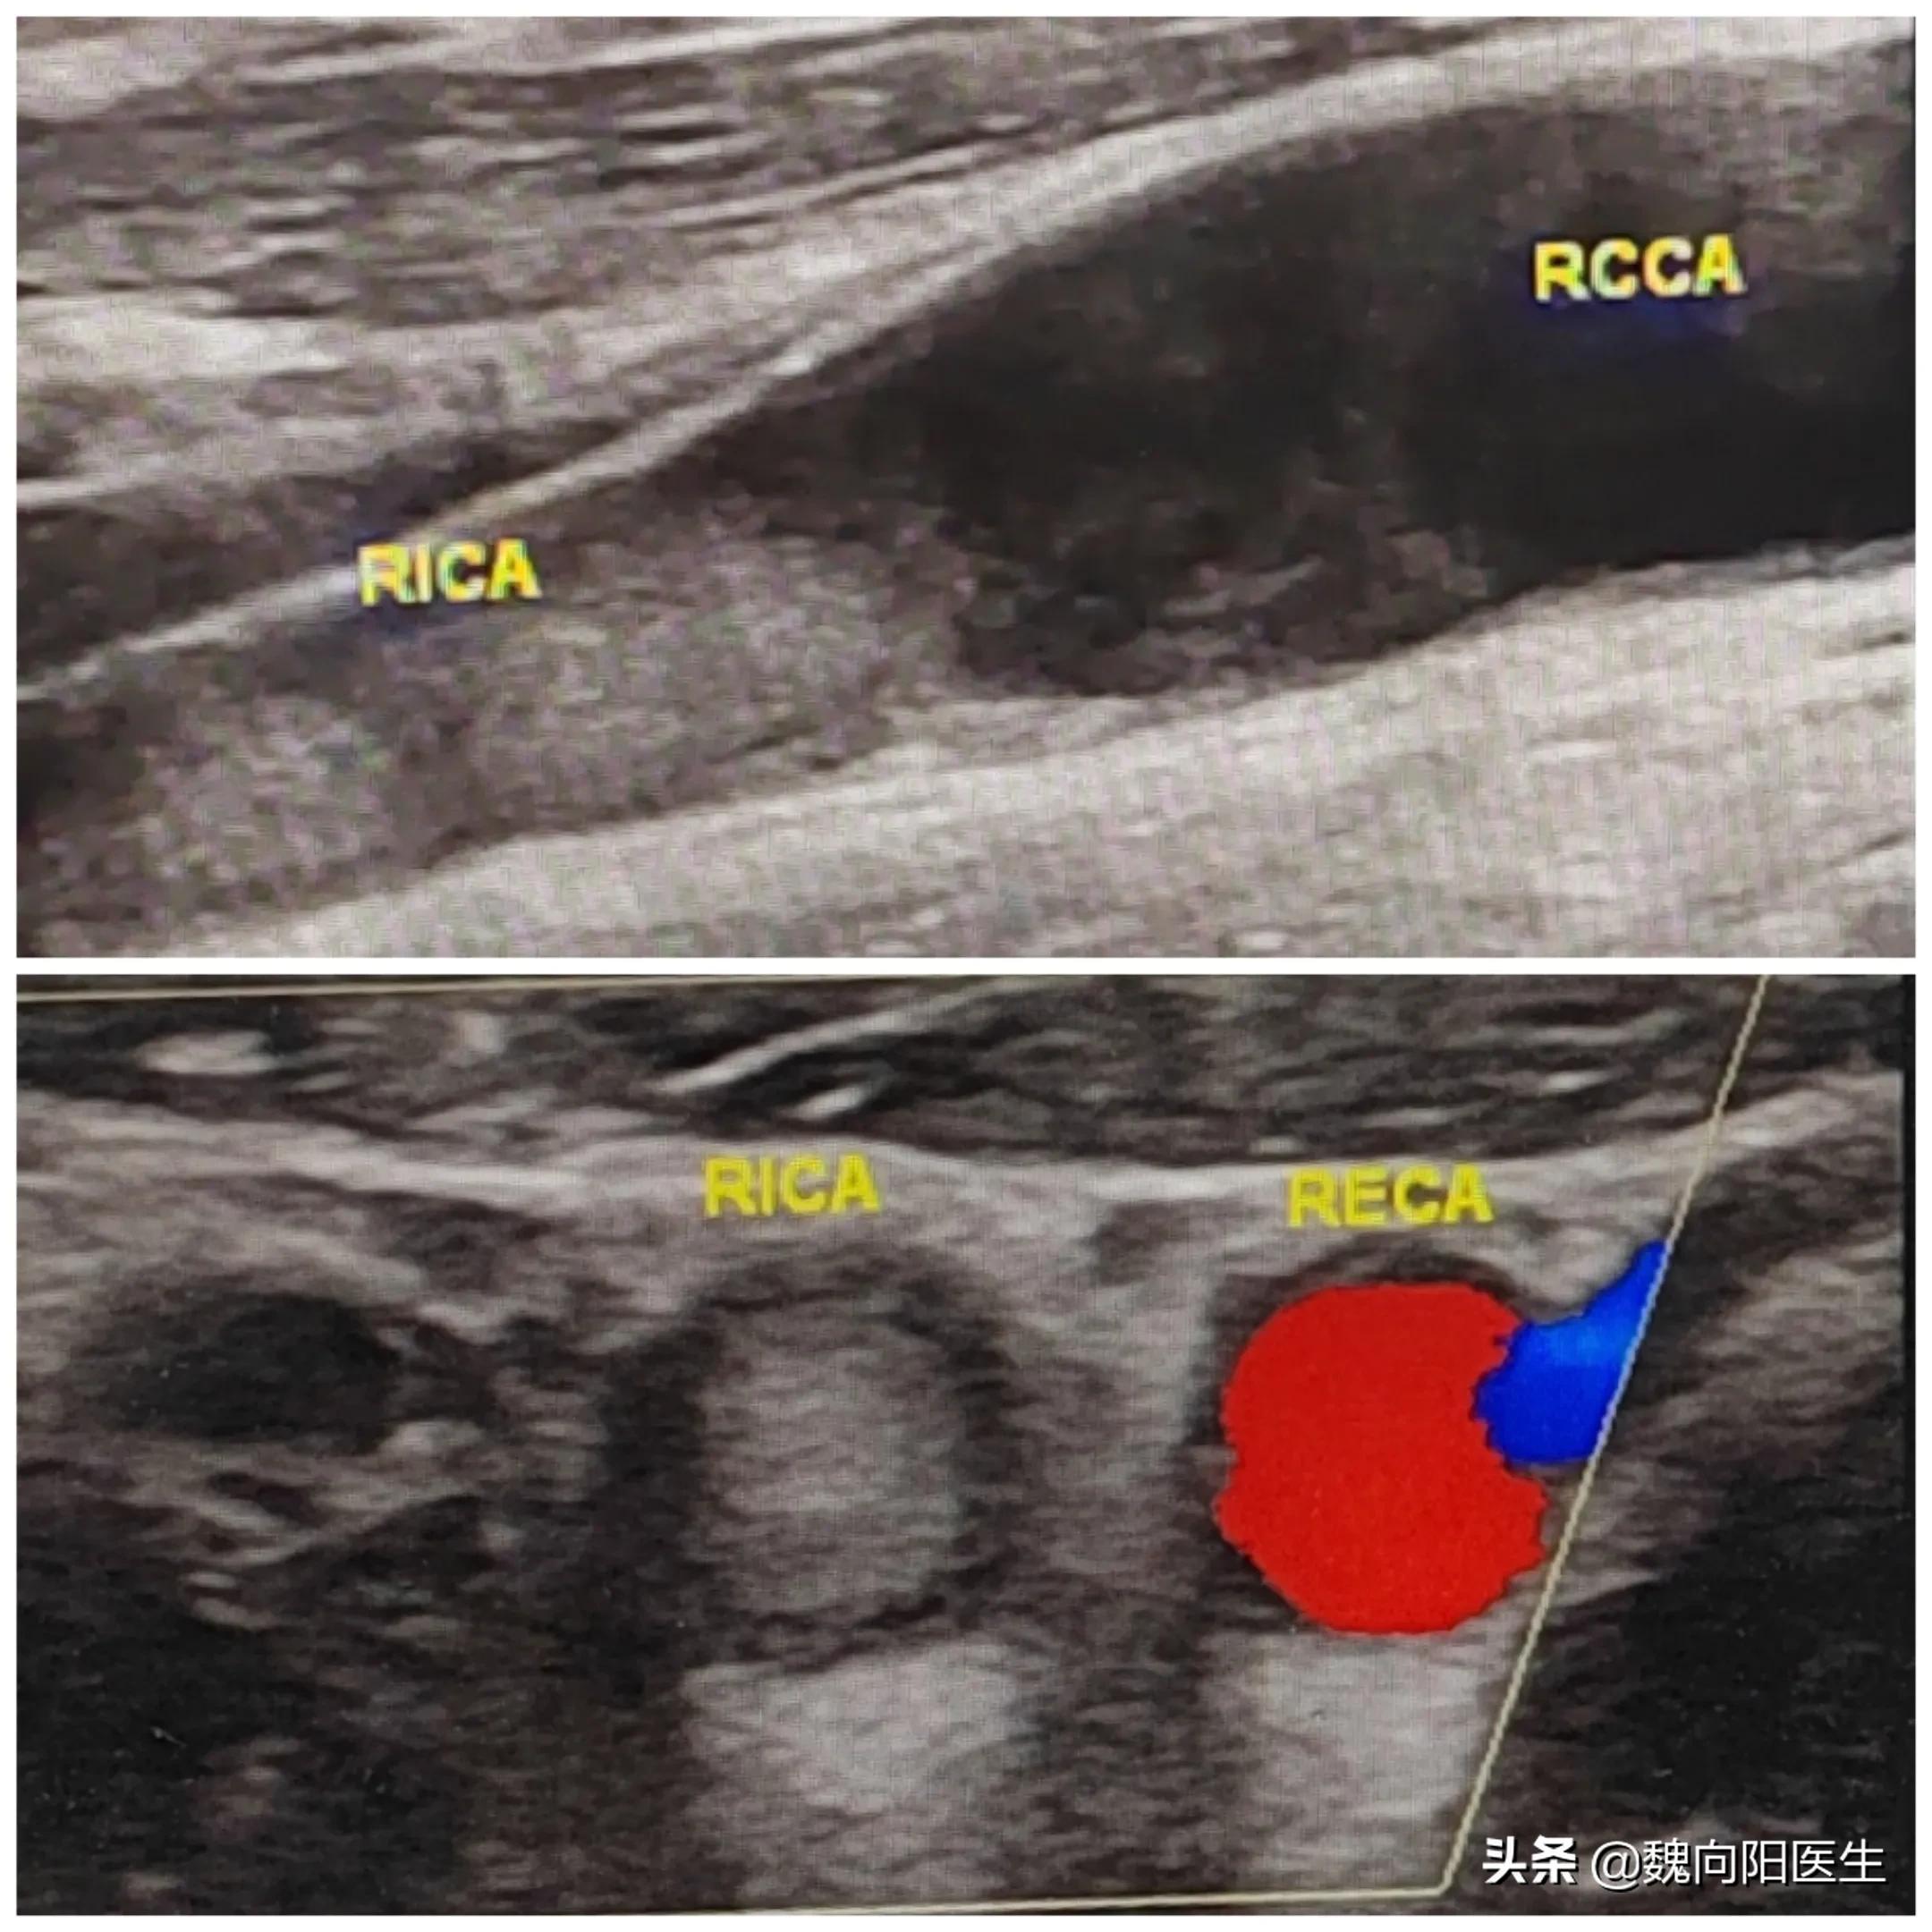

颈内动脉血栓

颈内动脉作为支配大脑半球主要供血的血管主干,一旦发生急性闭塞,会导致致命性的大面积脑梗死发生。